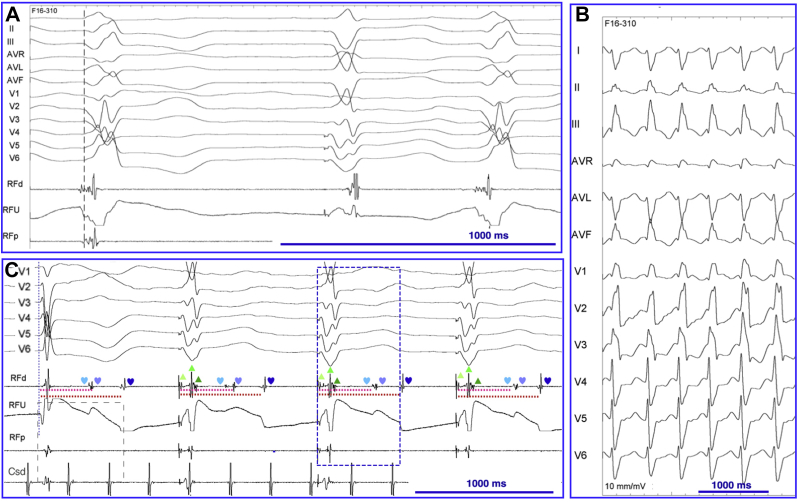

A 72-year-old woman with a history of heart failure secondary to ischemic cardiomyopathy, coronary artery bypass graft surgery, and cardiac resynchronization therapy (CRT) presented with functional deterioration (NYHA class III). She was treated with apixaban, aspirin, bisoprolol, candesartan, bumetanide, pravastatin, pantoprazole, and sertraline. There was no indication for additional coronary revascularization. Ablation of the PVCs was planned for symptomatic and prognostic reasons. Her electrocardiogram (ECG) demonstrated PVCs with a single morphology in bigeminy during biventricular pacing at 60 beats per minute with underlying left atrial flutter (Figure 1A). Interrogation of her CRT device revealed 50% biventricular pacing due to continuous bigeminy. Bigeminy was also present during atrioventricular conducted beats (Figure 1B), during right or left ventricular–only pacing, and during biventricular pacing at 80 beats per minute (Figure 1C). Two different PVCs were identified with a similar coupling interval of 630 ms.

A: Baseline electrocardiogram (ECG) during biventricular pacing at 60 beats per minute showing an underlying left atrial flutter and bigeminy. The premature ventricular complexes have the same morphology and a coupling interval of 630 ms, indicated by the blue rectangle. B: Baseline ECG, after reprograming the lower pacing rate at 30 beats per minute, showing poor residual atrioventricular conduction with narrow QRS complexes and 2 different morphologies of premature ventricular complexes (PVCs) with the same coupling interval (580 ms). The red line corresponds to the beginning of the narrow QRS complexes. The blue rectangles indicate a longer PVC coupling interval (630 ms) during biventricular pacing at 60 beats per minute. C: Biventricular pacing at 80 beats per minute showing bigeminy with the same 2 different PVC morphologies. PVCs alternate and have a similar coupling interval compared with biventricular pacing at 60 beats per minute (blue rectangle).